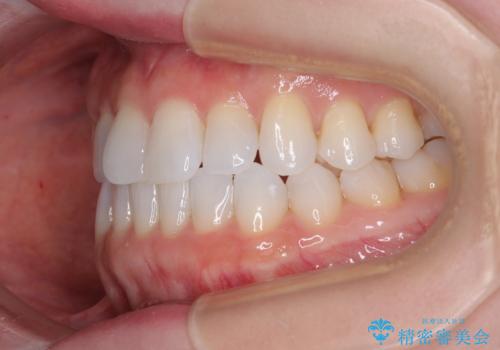

前歯のデコボコをインビザラインで綺麗に

- 上下前歯の叢生を気にして来院された患者様です。

インビザラインでの治療を希望されていて、デコボコの程度が中等度であり、安価なパッケージにて対応可能と判断されたため、インビザライン・モデレートを用いて矯正治療を行うこととしました。

インビザライン・モデレートは、製作できるアライナーの枚数に制限があるため、移動可能な量に限りがあるものの、インビザライン・ライトよりも枚数が多いため、幅広い症例に対応可能です。